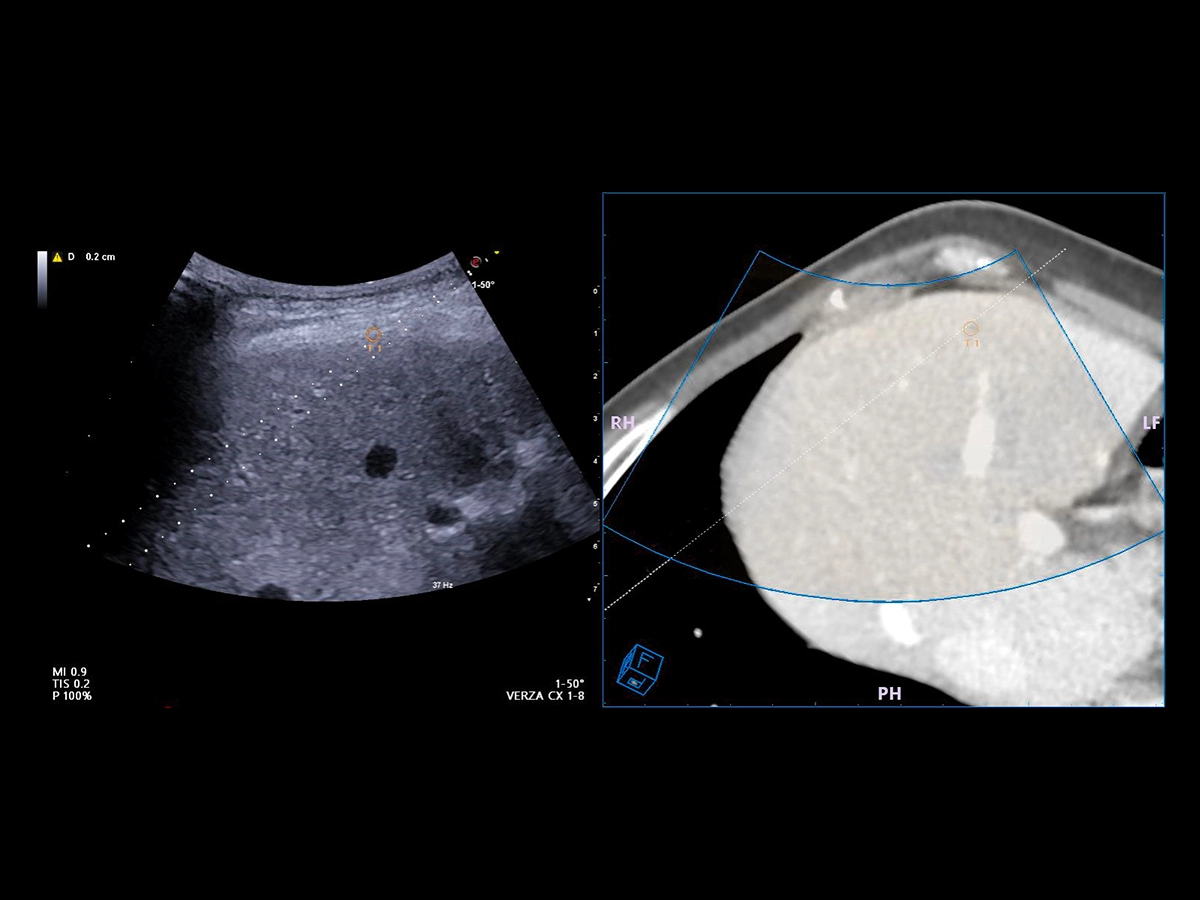

Virtual Navigator (VNav), as the most advanced Esaote Fusion Imaging technology supported by Artificial Intelligence, is opening new horizons in cross-modality liver imaging. Virtual Navigator provides a very simple and active coupling of ultrasound examination with a second Dicom modality imaging (MRI/CT/Pet-CT) dataset as a reference. It enables real-time navigation to benefit from both modalities to increase confidence and accuracy throughout interventional procedures on the liver.

Virtual Navigator will bring you particular support when you face complicated liver pathologies or conditions during your procedures, particularly in the following cases:

• Lesions which are better identified with CT, MRI, and PET or slightly visible in US

• Lesions which are only visible during arterial phase enhancement

• Follow-up of local tumours after ablation or resection

• New lesions in subsequent follow-up surgery or ablation.

• Hidden lesions during treatments (gassed out US).

• Composite ablations requiring multiple needle insertions.

• Complex geometries or difficult treatment planes to identify a safe pathway to the target, such as a difficult US “window”, or complex angle of insertion.